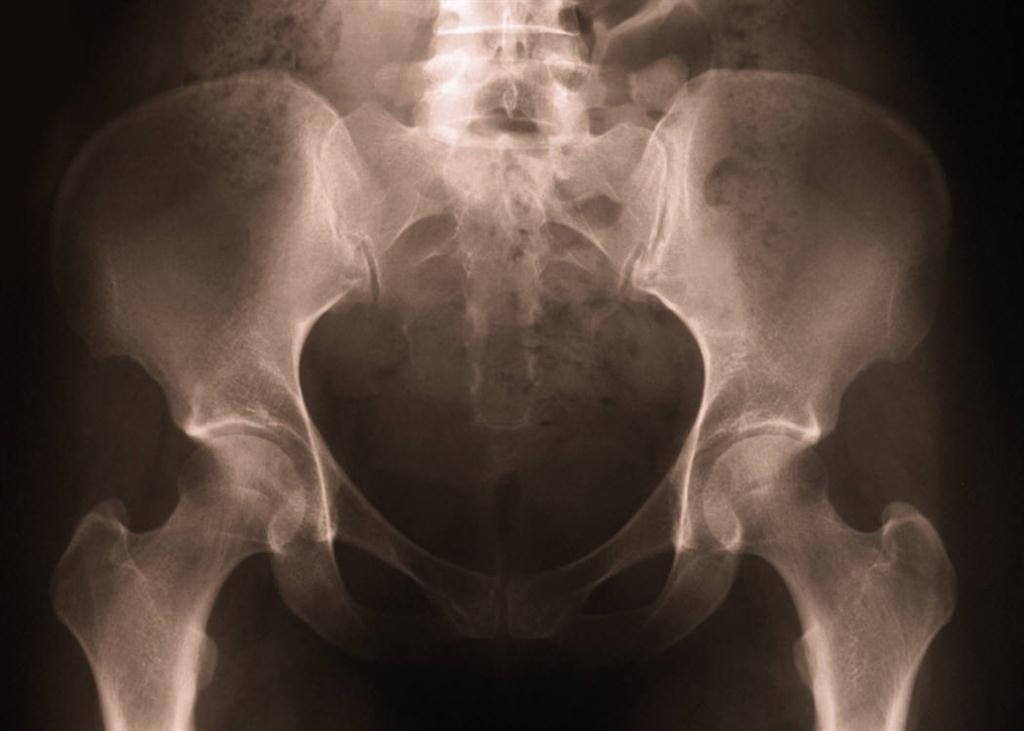

Hip Fracture? Watch Out for Vertebral Fractures.

Of 458 hip fracture patients, 69% of women and 60% of men had at least one mild vertebral fracture while 16% of women and 17% of men had at least one severe vertebral fracture. Those are high percentages in patients who just experienced a hip fracture. (5) Let Aurora Chiropractic Center be a part of your Juneau hip and vertebral fracture prevention healthcare team.